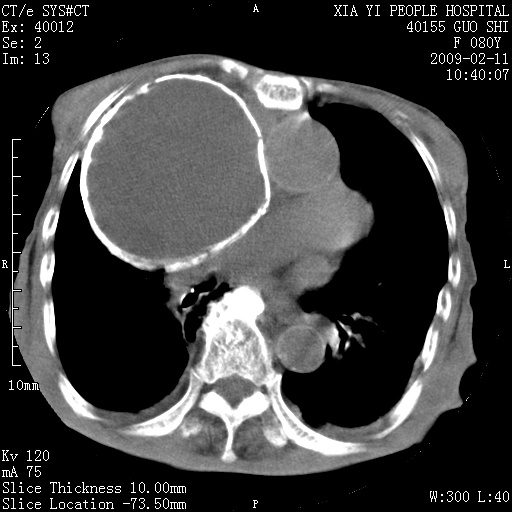

以下是引用随光逐影在2009-2-16 16:34:00的发言:[br]1)考虑右前纵隔皮样囊肿。2)双侧少量胸腔积液。

以下是引用zjzjr在2009-2-16 17:30:00的发言:[br]支持囊性畸胎瘤 双侧少量胸腔积液。